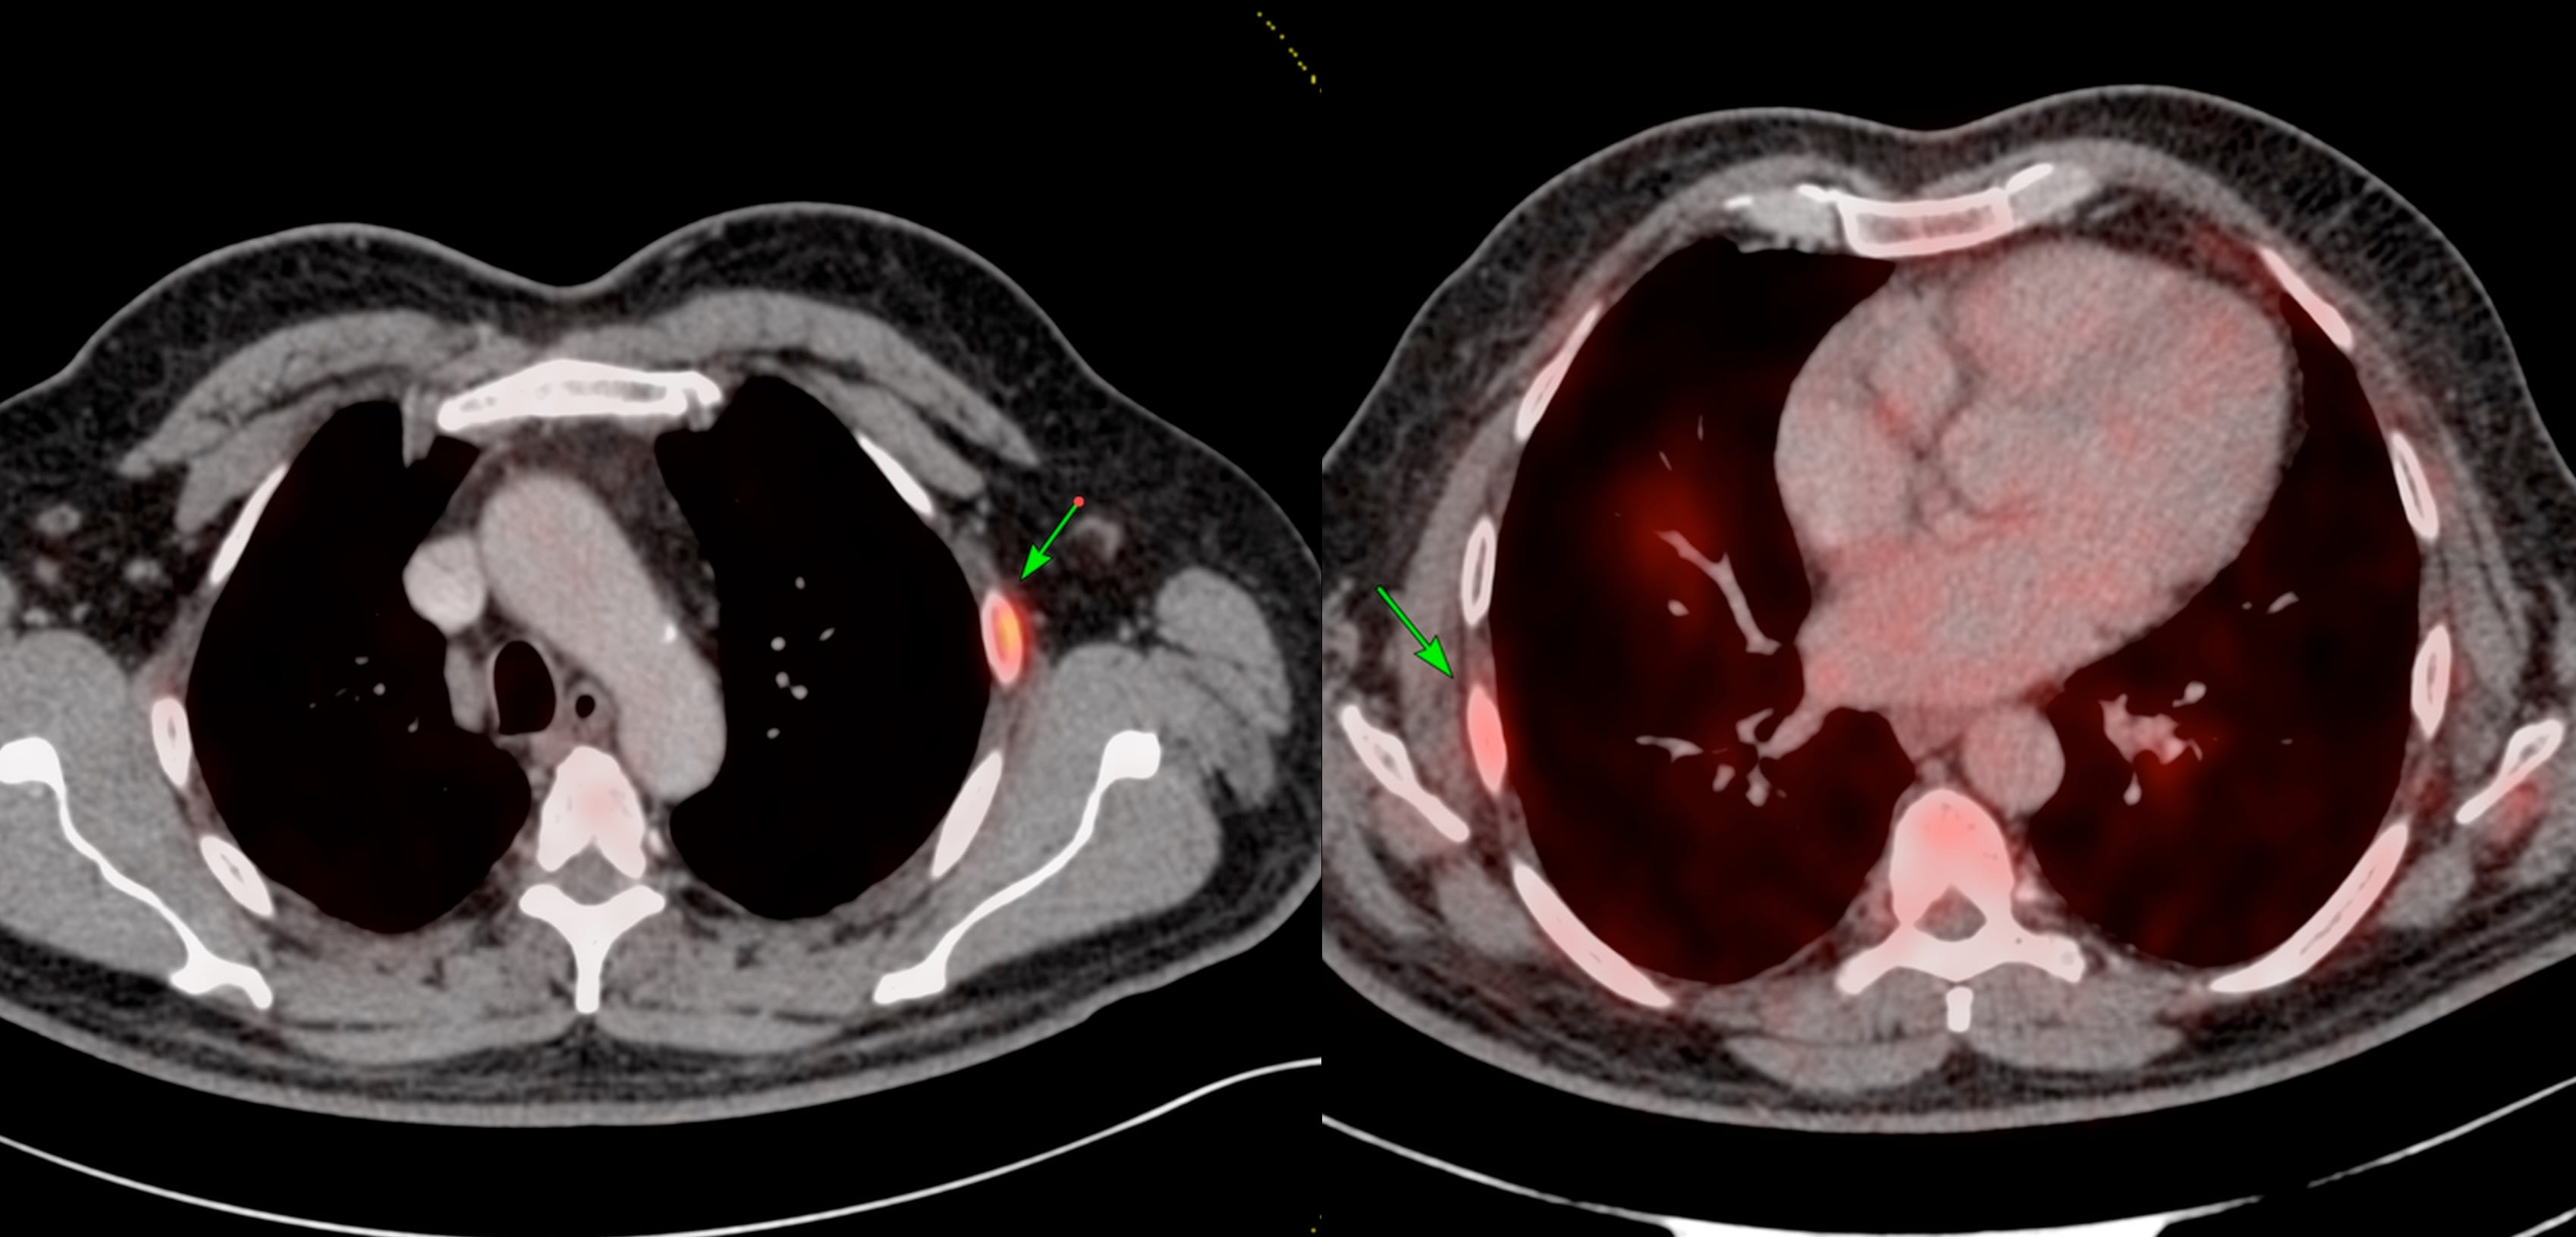

One paper (Fig. 3) has these statistics - 52% of biopsy-negative lesions were in the rib and only 26% of all rib biopsies performed for metastatic cancer were positive in patients who had PSMA positive rib uptake.

Takeaway - isolated rib uptake on PSMA PET should be viewed with caution and should not be automatically assumed to be metastatic disease. These lesions should be worked up carefully assuming they are benign unless proven otherwise.